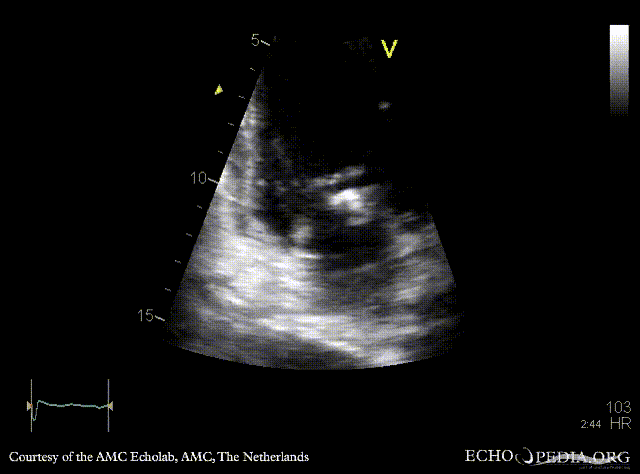

Endocarditis of mitral valve

A5CH A5CH: Color doppler, severe mitral regurgitation

A3CH: Color doppler, severe mitral regurgitation Continuous-wave signal of tricuspid regurgitation, increased SPAP